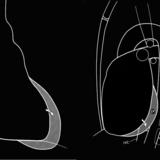

Left chambers Lat